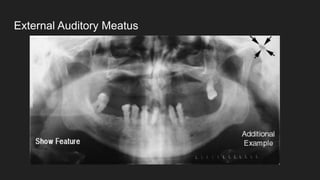

● External auditory meatus

External Auditory Meatus